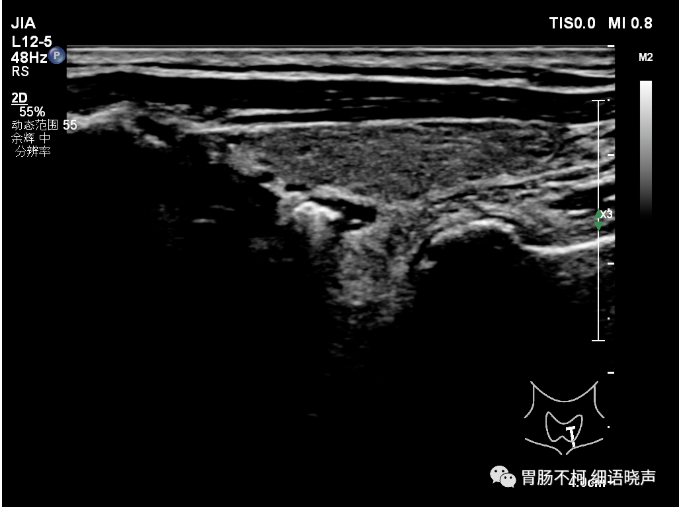

病例三:甲状腺左叶后方混合回声型食管Killian-Jamieson憩室,低回声内见点状强回声。